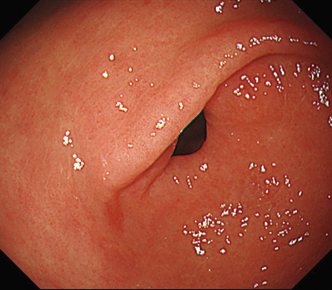

EVIS LUCERA ELITE × GIF-1200N 、EVIS X1 × GIF-H190N 什器比較画像

面順次式、同時式で色味の違いはありますが、どちらもハイビジョン画質にて観察可能です。

EVIS X1×GIF-H190N